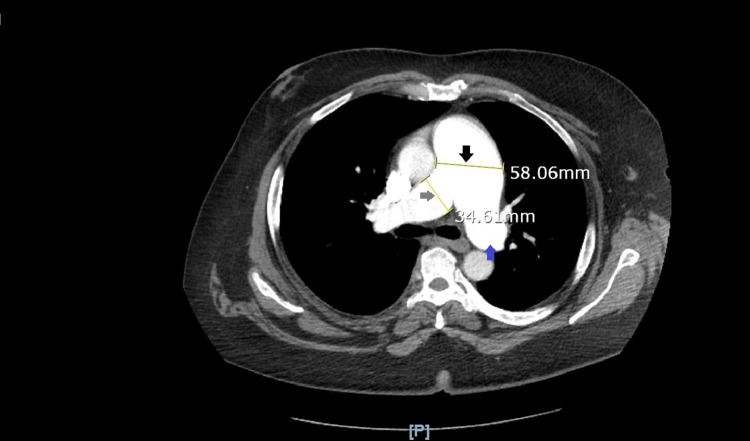

CT pulmonary angiogram (Fig. 3) identified MPA dilatation with a diameter of 5.8 cm, right pulmonary artery dilatation with 3.5 cm diameter, left pulmonary artery dilatation with 3.3 cm diameter, right hemidiaphragm elevation, and hepatomegaly.

Fig. 3.

Pulmonary artery aneurysm on CT-PA: pulmonary artery is measured as 58.06 mm (5.8 cm) which is greater than the normal diameter of 2.9 cm, hence this CT-PA image confirms pulmonary artery aneurysm formation (black arrow). This image also marks the dilated right pulmonary artery (34.61 mm, grey arrow) and dilated left pulmonary artery (blue arrow).